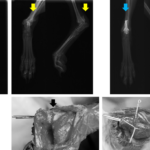

【症例紹介】踵骨骨折(かかとの骨折)